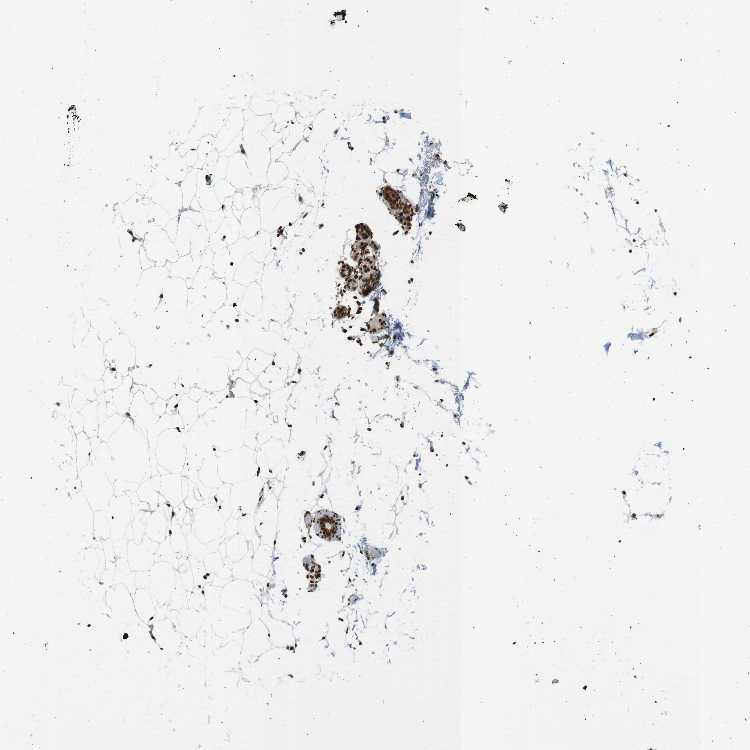

SOFT TISSUE 1 - Antibody stainingi

Antibody staining in the annotated cell types in the current human tissue is reported as not detected, low, medium, or high, based on conventional immunohistochemistry profiling in selected tissues. This score is based on the combination of the staining intensity and fraction of stained cells.

Each image is clickable and will lead to virtual microscopy that enables deeper exploration of all samples and also displays staining intensity scores, fraction scores and subcellular localization as well as patient and tissue information for each sample.

Antibody HPA067966Antibody CAB012432

Chondrocytes Not detectedHigh

Fibroblasts Not detectedHigh

Peripheral nerve Not detectedHigh